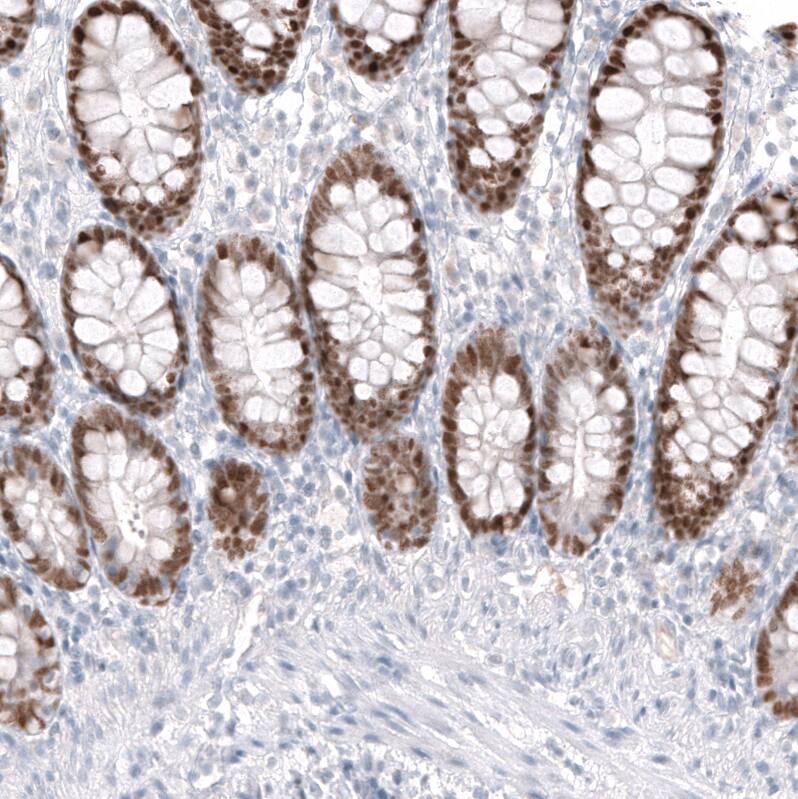

Staining of human colon shows moderate to strong nuclear positivity in glandular cells.

Staining of human rectum shows strong nuclear positivity in glandular cells.